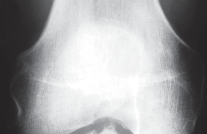

التصوير الطبي ضروري لتأكيد التشخيص وتحديد مدى تلف المفصل:

-

الأشعة السينية العادية (Plain Radiographs):

- المنظر الأمامي الخلفي (AP): يُظهر الركبة من الأمام.

- المنظر الجانبي (Lateral): يُظهر الركبة من الجانب.

- المنظر الخلفي الأمامي المثني (PA Flexed): يسمح بتقييم أفضل للجزء الخلفي من الركبة وقد يكشف عن تغيرات أكبر في الحجرة الخلفية الوحشية.

- منظر شروق الشمس (Sunrise/Patellofemoral): لتقييم المفصل الرضفي الفخذي.

- الأشعة السينية الطويلة للطرف السفلي بالكامل (Full-length standing radiographs): من الورك إلى الكاحل، وهي مفيدة جدًا، خاصة إذا تم استخدام تقنيات الملاحة الحاسوبية. تُظهر هذه الأشعة المحاذاة الكلية للطرف السفلي.